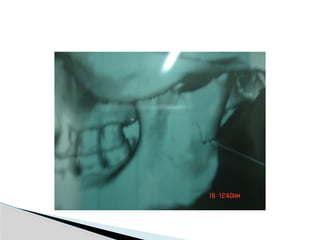

Conventional Radiology

At least 2 views at right angle to each other.

Mandibular series: PA, Lateral oblique or

panoramic, & Towne’s view (projects condyle

below mastoid process).

Conventional Radiology At least2 views at right angle to each other. Mandibular series: PA, Lateral oblique or panoramic, & Towne’s view (projects condyle below mastoid process). CT Significant displacement or dislocation, mechanical obstruction, mult trauma pt, & intracapsular fracture. MRI St injuries: effusion, visualization of disc. Imaging